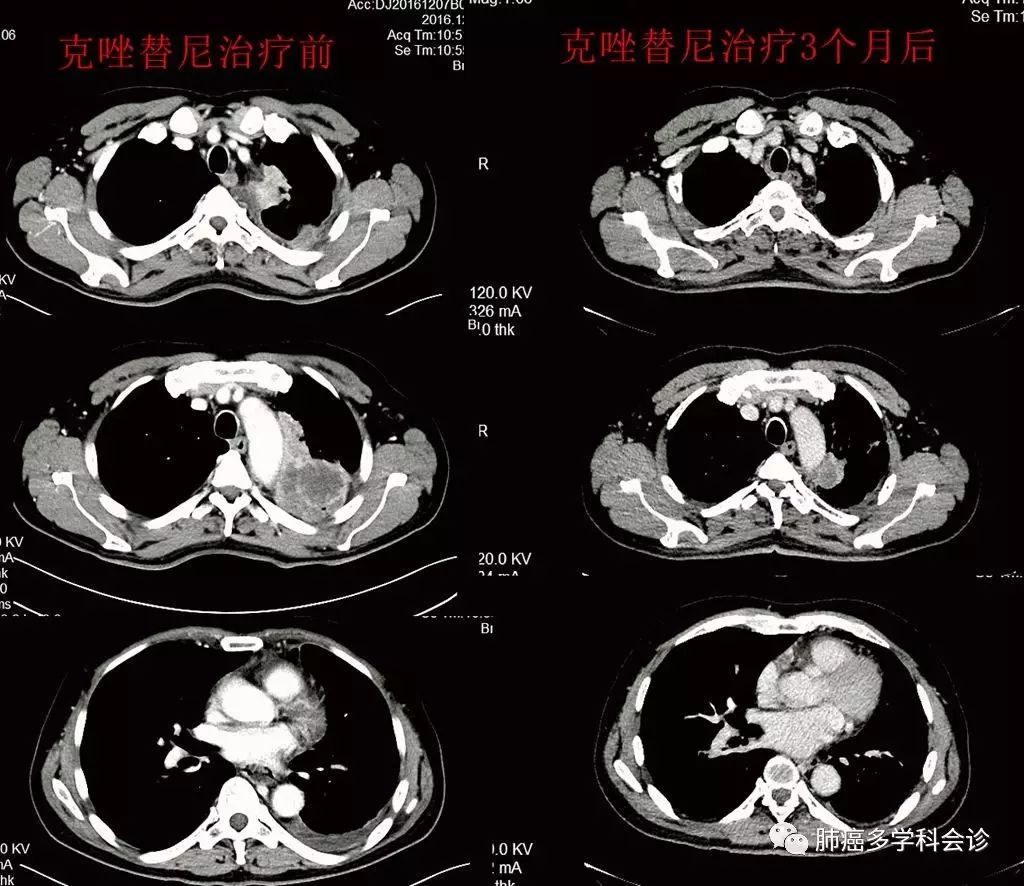

于2016-12-22开始口服克唑替尼,20余天后复查CT示病灶稳定,3月后复查CT示疗效PR,肿瘤标志物 CA19-9 明显下降。